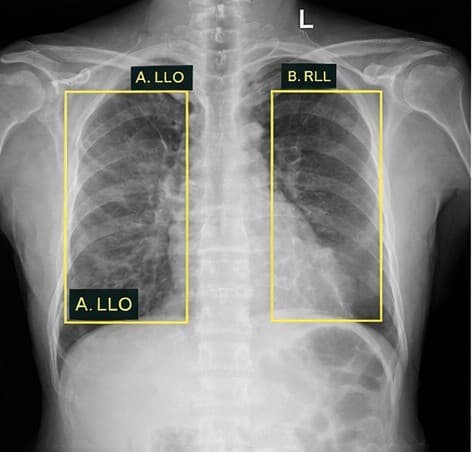

Lung tumor

Tuberculosis

TB | 0.94Sputum collection pending

Tuberculosis | 0.94Sputum collection pending